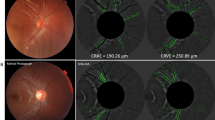

The images were filtered in two ways (1) “skeletonized”, and (2) “contrast-enhanced” Fig. 1.

The Vesselness measure indicated the probability of a pixel being a vessel. Thresholding was applied and all pixels with a probability higher than the threshold value were assigned as pixels belonging to a vessel Fig. 1B.

where * denotes the convolution operation, I denotes input image and G(ρ) represents the Gaussian filter with a standard deviation of ρ19 Fig. 1C. These images were then normalized to prevent the well-documented CNN “gradient explosion problem”40.

Representative examples of the attention maps derived from the contrast-enhanced fundus image dataset are shown in Fig. 4. Attention maps were not generated from the skeletonised image dataset as this CNN failed to reach 80% accuracy. Within the attention map the retinal vessels, the perivascular region and the fovea have been highlighted, indicating that the CNN used data from these areas when making its decision on the smoking status of the image under test. The attention maps were similar for all the analysed images and there was no visually identifiable difference between the attention maps derived from the images that were obtained from smokers compared to those from non-smokers.

In highlighting the retinal vasculature, the perivascular region and the fovea, the attention maps derived from the analysis of the contrast-enhanced image dataset, demonstrate that the CNN has identified these regions on the images as being the most important for predicting the smoking status. A wider retinal venular calibre has previously been reported to be linked to smoking10,11, so the finding that the retinal vasculature is highlighted on the attention maps suggests that the CNN is, at least in part, deriving a conclusion based on these structural changes. Similar findings were reported by Poplin, et al.35, although a lower accuracy 0.71% (0.70–0.73%) as measured by AUC, and using non pre-processed fundus photos. We believe that the main reason why our network outperformed the previous study has been the use of pre-processed fundus photos, as oppose to unprocessed images. We believe that providing our CNN with ‘contrast enhanced’ features of the perivascular region has assisted with its classification task. The observation that removing this region of fundus photos in our ‘skeletonized’ images led to much poorer performance would further support this hypothesis. Meanwhile, it is interesting to observe that a CNN trained on skeletonised images, a pre-processing method, which reduces the image to a geometric representation of vasculature isolated from the rest of the fundus, is unable to accurately classify the smoking status of the images. It suggests that changes in the architecture of the vasculature, such as vessel calibre6,7,8,9,10,11,12, vessel tortuosity and bifurcation5, and vascular fractal dimentions15,16,17 alone are not sufficiently strong predictive markers for the accurate detection of the smoking status of an individual who has diabetes.

Whilst it is difficult to identify with any certainty why the skeletonised model failed to accurately predict whether an individual smoked, this model does not make a clear a distinction between the retinal arteries and veins and it includes some of the larger choroidal vessels Fig. 1. This lack of clarity between the different components of the retinal vasculature and the inclusion of some of the larger choroidal vessels may have introduced noise into model, which reduced its accuracy. Moreover, the finding that the paravascular area and fovea in the contrast-enhanced images are also important indicates that the CNN is deriving important predictive data from these areas. Both hypertension and dyslipidaemia are associated with well recognised changes within the retinal vasculature45,46,47,48 and it is therefore possible that the paravascular changes that the algorithm used to classify the images were based, at least in part, on these changes. However, the relationship between chronic cigarette smoking and hypertension is inconclusive with large epidemiological studies concluding that any independent chronic effect of smoking on blood pressure is small49,50. The one exception perhaps being older male smokers had higher systolic BP adjusted for age, BMI, social class, and alcohol intake compared to matched non-smoking peers51. Moreover, nearly two thirds of patients in our study were on treatment for hypertension, and the proportion of patients who were being treated for hypertension was similar between those who identified as smokers, compared to those who identified as non-smokers. These data are likely to reflect that patients with diabetes will have their blood pressure checked regularly as part of their regular systemic review and be treated appropriately. One has to acknowledge that an individual being on treatment for hypertension, is not the same as knowing what their blood pressure is. It is therefore still possible that the cohort who identified as smokers had more signs of hypertensive retinopathy compared to non-smokers. However, as the majority of these individuals were regularly being reviewed by their physician, and that the blood pressure targets for each cohort would be similar, it is probably reasonable to assume that the blood pressure control in both cohorts was also similar. The finding that the HbA1C was very similar in each cohort suggests that the management of their diabetes and associated co-morbidities was similar across groups. Resolving this uncertainty would require the retinal images to be labelled with either the blood pressure at the time of image acquisition, and/or whether hypertensive retinopathy was present. However, this data was not available to us so we were unable to test this hypothesis. The possible influence that dyslipidaemia had on the function of our algorithms can be addressed with a very similar set of arguments, but again we did not have the data, which would allow us to interrogate this association any further.